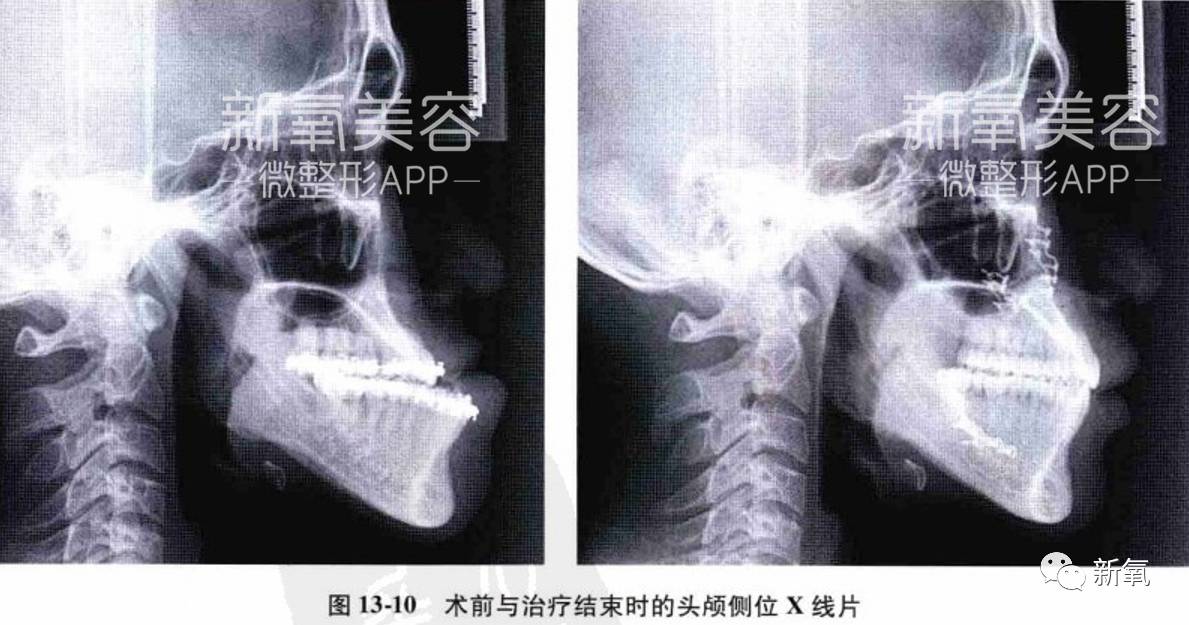

没有牙齿、后天习惯的影响,下颌骨本身也有可能发育不良导致外貌改变,比如遗传。下面左图的这种严重下颌骨发育不良甚至导致了张口困难,更专业的名称叫双关节骨性强直伴小颌畸形。

到这种程度的下颌问题,就需要分期联合治疗了。